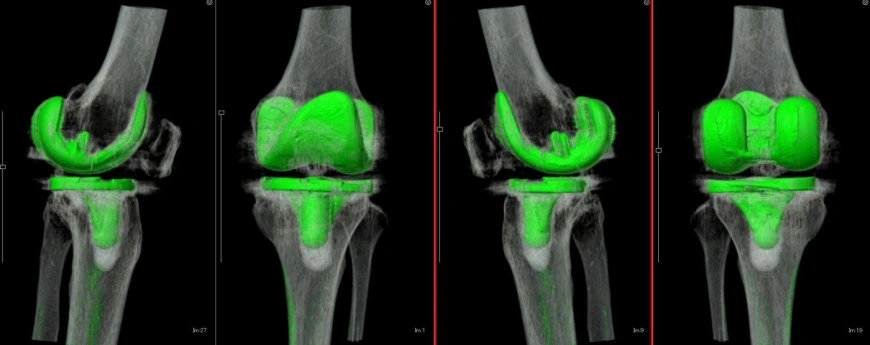

左TKA術後3D